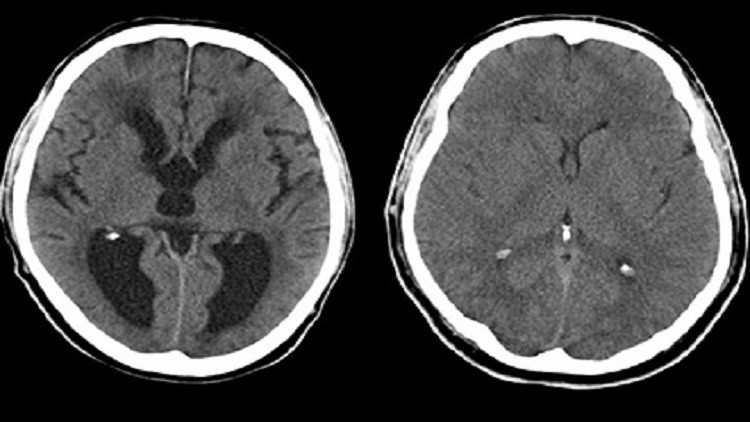

العلماء يحددون أسباب “استسقاء” الرأس عند المواليد الجدد

توصل علماء من الولايات المتحدة إلى نتائج جديدة حول أسباب استسقاء الرأس أو ما يعرف بتراكم السائل الدماغي في تجاويف وجيوب دماغ المواليد الجدد.

وأكد العلماء أن التجارب على الفئران أظهرت أيضا أن “الاستسقاء الرأسي” التي تصاب به القوارض سببه مشاكل في الخلايا “البطانية” لبعض تجاويف الدماغ ما يؤدي إلى تراكم السوائل في تلك التجاويف، ومشاكل الخلايا تلك يعود سببها إلى فقدان بروتين  SNX27.